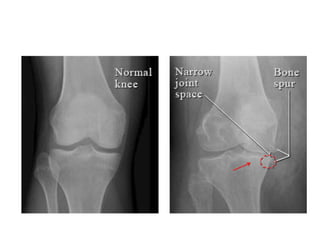

RADIOLOGIC FINDINGS OF OA

• Narrowing of joint space

(due to loss of cartilage)

• Osteophytes

• Subchondral (paraarticular) sclerosis

• Bone cysts

OA OF KNEE JOINT

 More common in obese females

 over 50 years of age

 Joint stiffness (<30 minutes)

 Mechanical pain

 Physical examination findings: Crepitus

 Pain on pressure

 Painful ROM and functional limitation

 Limitation of ROM in later stages of OA (first

extension)

 Laboratory analysis within normal limits